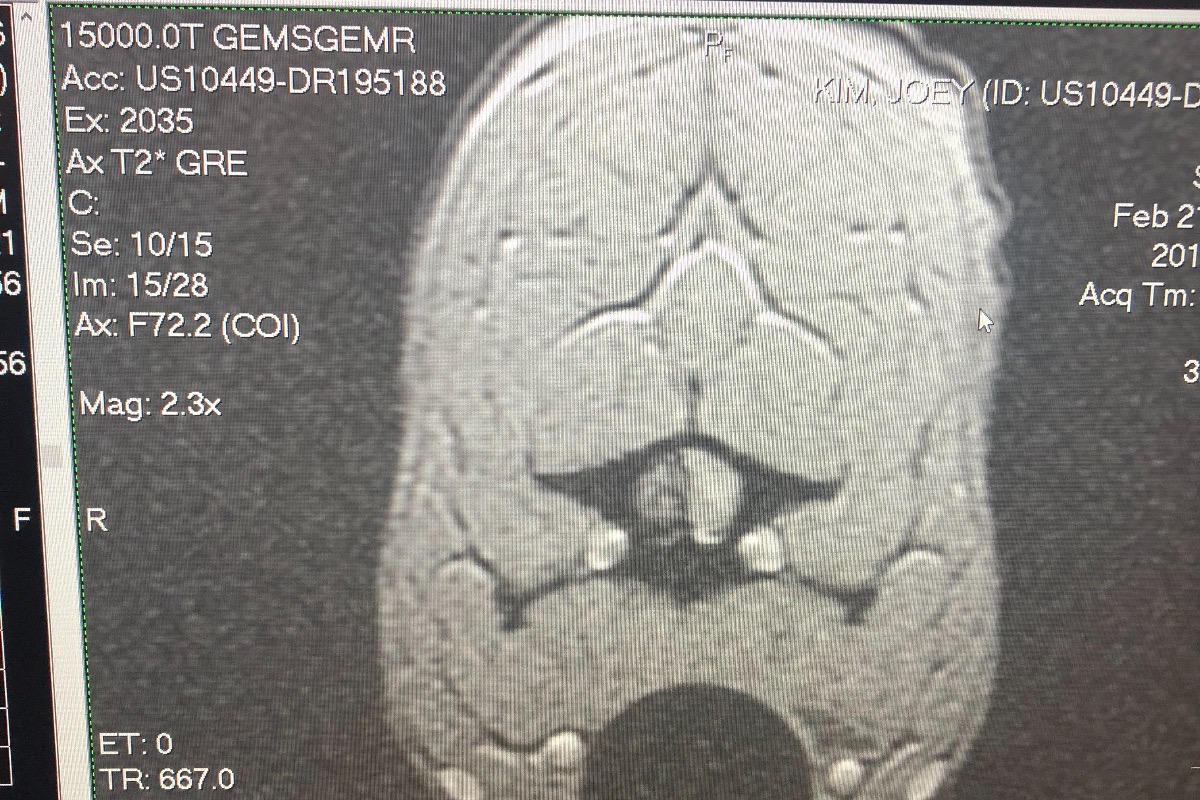

Diagnosis

(As well as I can recall) Slipped disc, spinal cord compression causing paralysis, above average hemorrhaging.

Diagnosis

(As well as I can recall) Slipped disc, spinal cord compression causing paralysis, above average hemorrhaging.